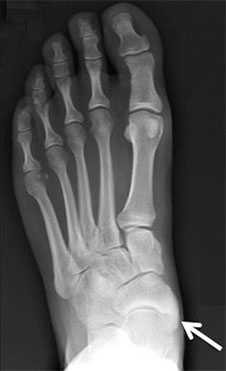

При первом вашем визите в клинику вам будет выполнена рентгенография стоп. Она поможет подтвердить диагноз, оценить тяжесть деформации и при необходимости спланировать хирургическое вмешательство.

Добавочная ладьевидная кость классифицируется в соответствии с рентгенологическими ее особенностями:

- Сесамовидная косточка в толще сухожилия задней большеберцовой мышцы в области его прикрепления к ладьевидной кости

- Добавочная ладьевидная кость, сочленяющаяся синхондрозом с ладьевидной костью

- Костный выступ ладьевидной кости

Рентгенограмма стопы при 1 типе добавочной ладьевидной кости

Рентгенограммы стоп: 3 тип добавочной ладьевидной кости